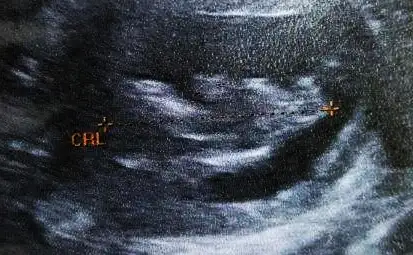

Havalianne__ bu da 7+3 günlük karından ultrason goruntum

7. Hafta karından ultrason görüntüsü. 27 mayıs 2016 son adet tarihi. Eşimin doğum tarihi 12 aralık 1980, benim doğum tarihim 1 eylül 1983...

Tahminin nedir canım?